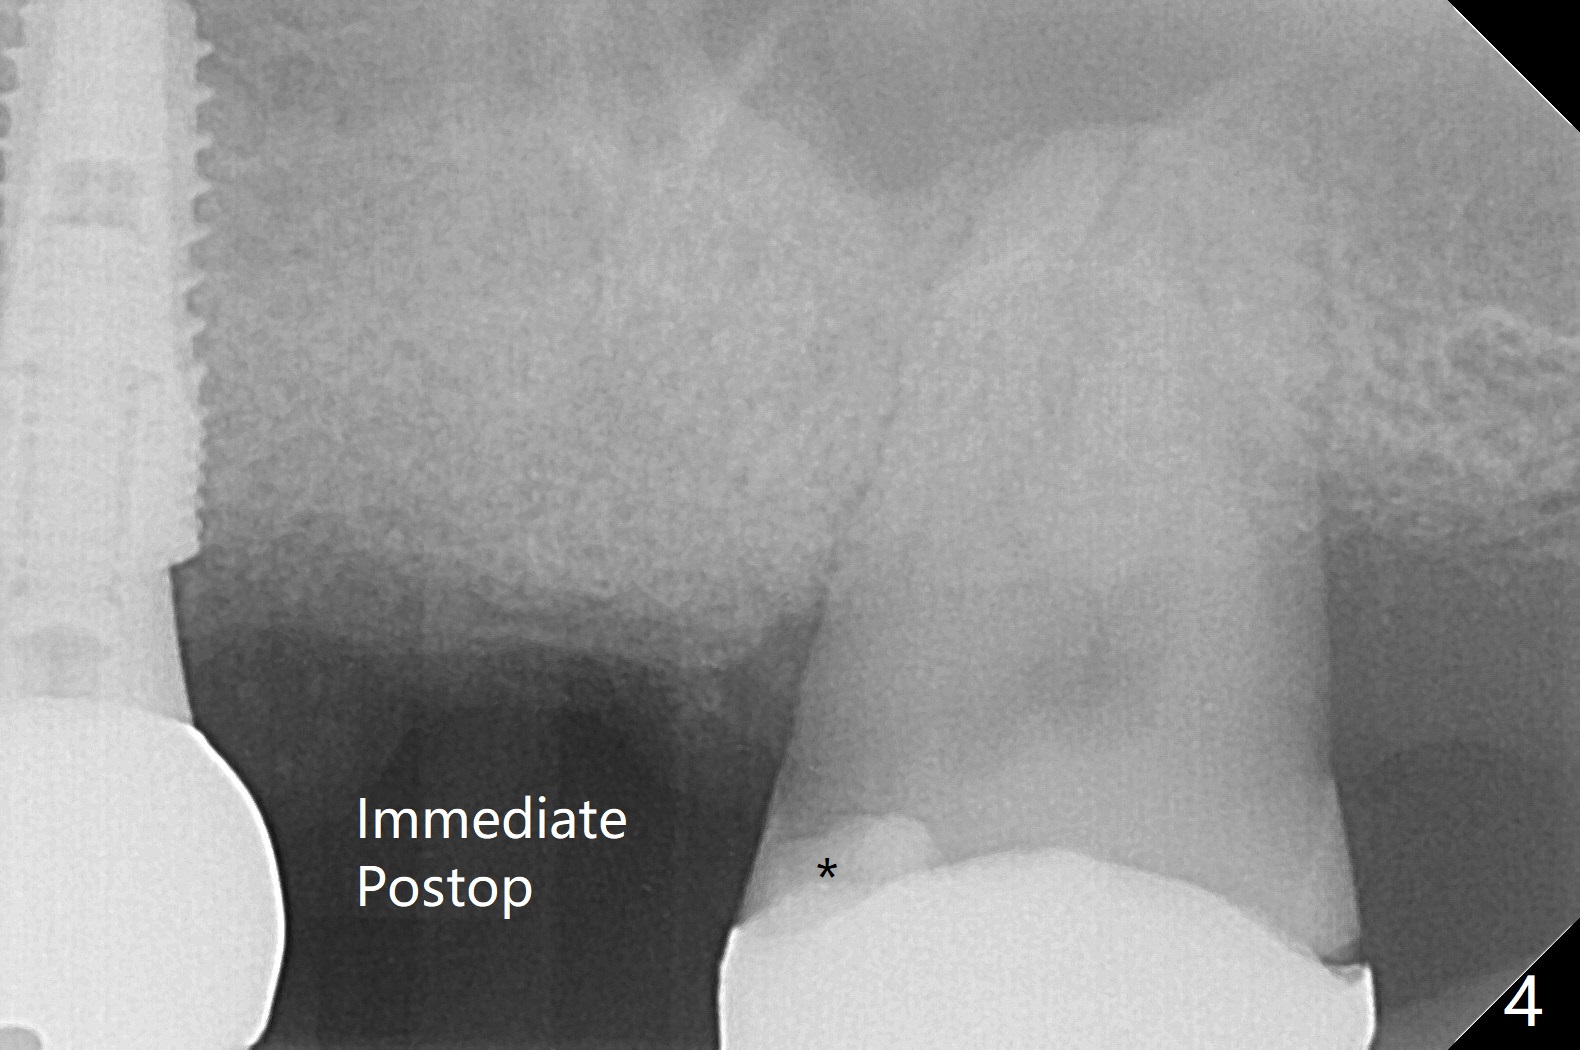

左上六拔除后,近中颊侧窝尤其大,与上颌窦相通(图一 *),而中隔比较尖,截除后还显得窄(图一,二:S),不太适合即刻种植。放置一块PRF膜于近中颊侧窝修补上颌窦,然后放置粘性骨块,好像有上颌窦提升迹象(图三:*(箭头:近中颊侧骨板缺失)),用骨粉填满其余牙槽窝(图四),覆盖另外一块PRF膜以及Cytoplast(不可吸收膜),用PTFE缝线(也不可吸收,与膜是同一个材料,非常柔软,好打结)缝合(图五)。最后使用牙周敷料。后者术后八九天脱落,病人术后十二天复诊,不可吸收膜腭侧有些外翻(图六箭头),伤口愈合尚可,没有骨粉丢失迹象,反复交代口腔卫生。再过三周撤除不可吸收膜。其实三周后膜自己脱落,病人回来撤去剩余缝线(图七),新鲜肉芽组织形成。术后5个月牙槽嵴和角化龈宽,骨高度尚可(图八),密度差些(图九,750单位),植体应该是4.5x8.5 或者 10 毫米,少量上颌窦提升。